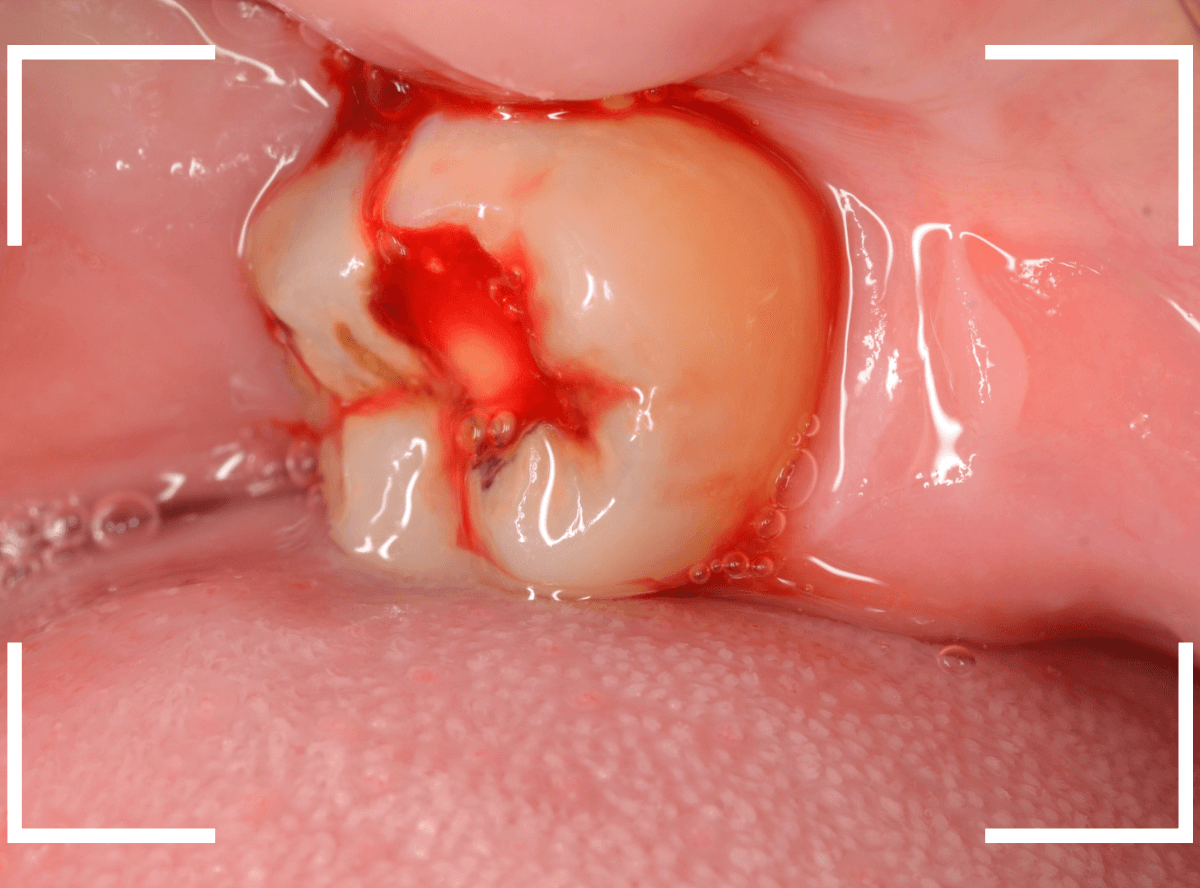

ここでは、比較的簡単なおやしらずの抜歯の例を中心にご紹介します。

このようなおやしらず、あなたはありませんか?